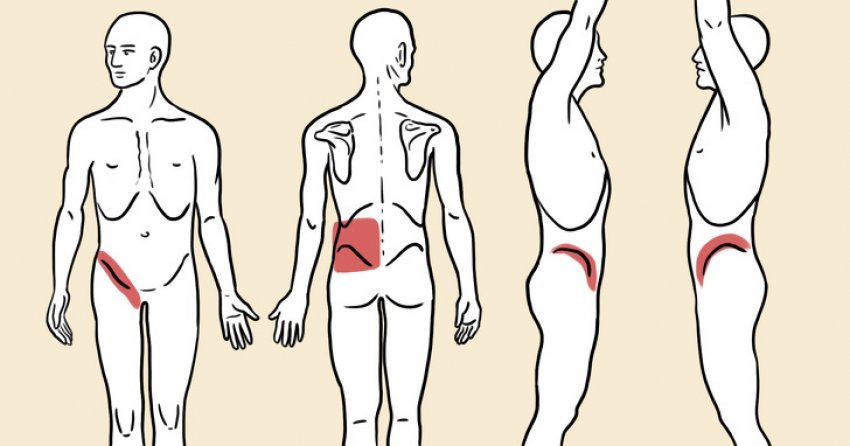

Bëni kujdes, këto janë shenjat që po ju paralajmërojnë se keni gurë në veshka

Bëni kujdes, këto janë shenjat që po ju paralajmërojnë se keni gurë në veshka

Njerëzimi e ka njohur problemin e gurëve në veshka që nga viti 600 para Krishtit.…